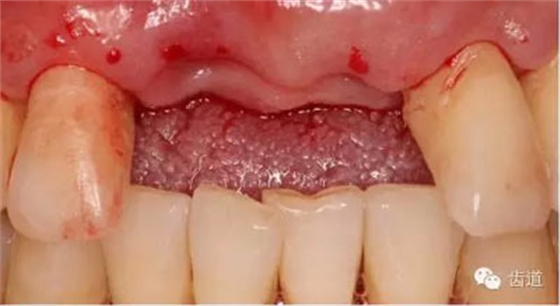

臨床檢查:

患者高位笑線,薄牙齦型。

11,21缺失。因外傷,導(dǎo)致11骨高度降低。

患者不愿才用自體骨移植,遂建議采用同種異體骨骨塊(皮質(zhì)骨)進(jìn)行骨環(huán)手術(shù)。 種植手術(shù):